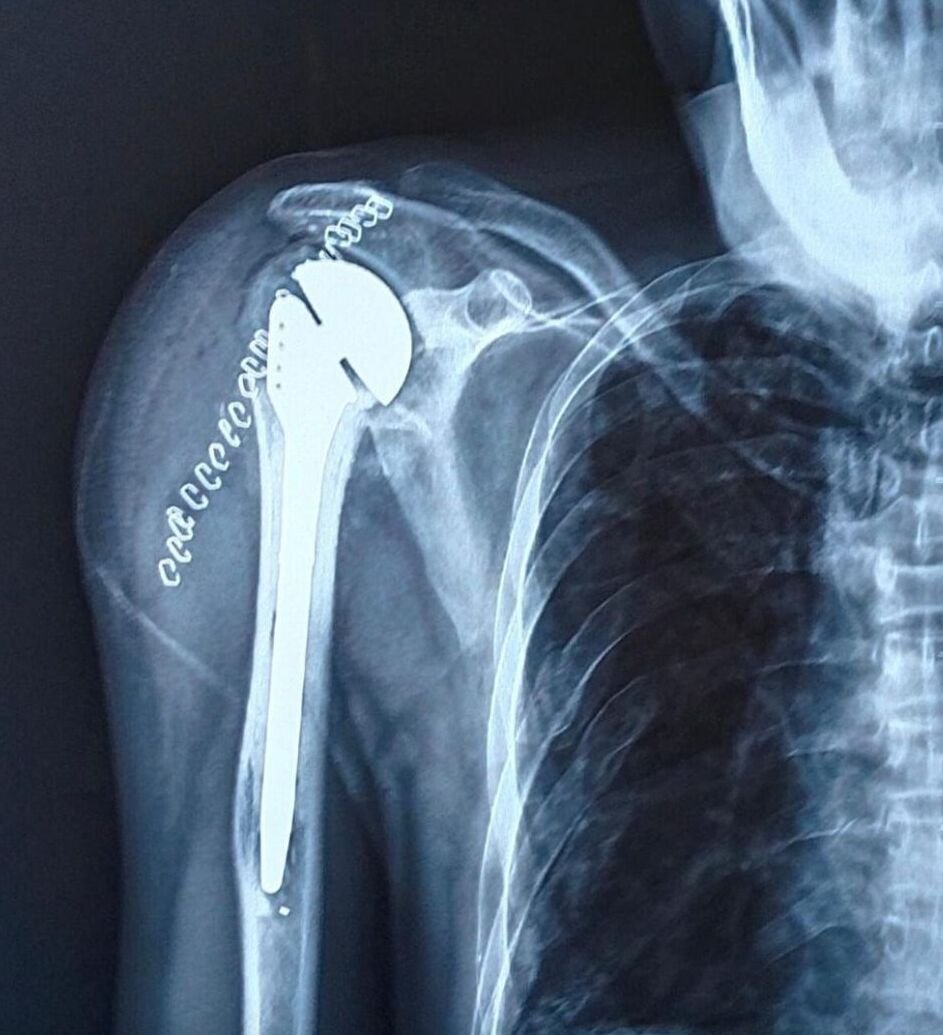

3. Shoulder Replacement:

Shoulder replacement surgery at Sachren Orthopaedic Hospital and IVF Centre is tailored to address severe shoulder arthritis or complex fractures. Our team uses the latest prosthetic designs and surgical methods to provide patients with improved shoulder function and pain relief.